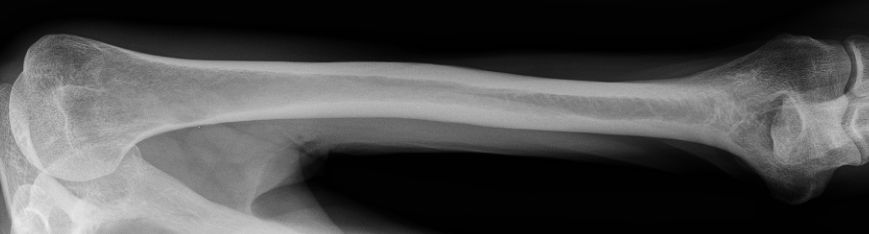

| Ulna | 54-jähriger Mann Adenokarzinom des li OL T4N3M1b. Im Knochenszintigramm fiel eine Mehranreicherung im mittleren Humerusschaft links auf.![]() | |||